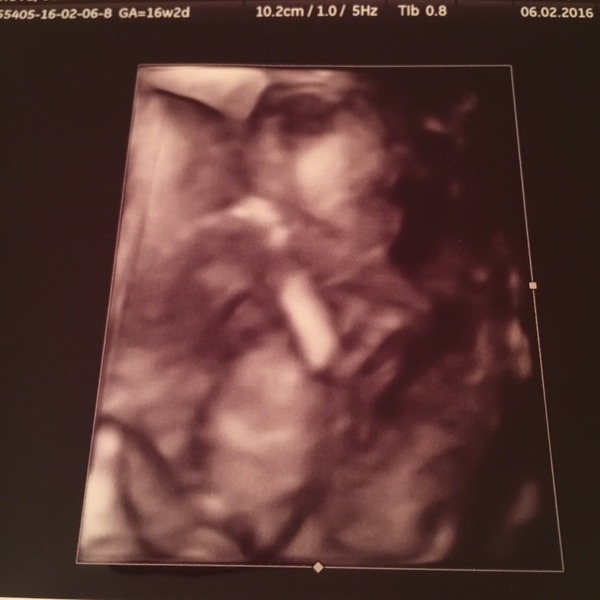

Ahh congrats!! Also team blue hopes Grin everything looked good too. Loved seeing 'him' again! I knew it was a boy!! My love of cheese had me convinced!

Lovely scan pic hope.